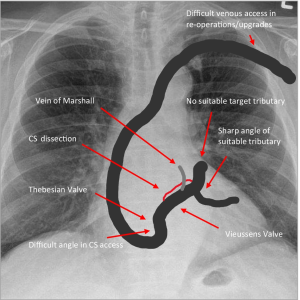

Definition: A combination of a CRT-P pacemaker and an ICD. It has three leads for resynchronization and can also deliver a life-saving shock.